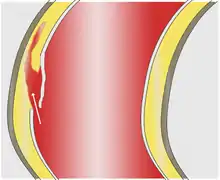

As with all other arteries, the aorta is made up of three layers, the intima, the media, and the adventitia. The intima is in direct contact with the blood inside the vessel, and mainly consists of a layer of endothelial cells on a basement membrane; the media contains connective and muscle tissue, and the vessel is protected on the outside by the adventitia, comprising connective tissue.[25]

In an aortic dissection, blood penetrates the intima and enters the media layer. The high pressure rips the tissue of the media apart along the laminated plane splitting the inner two-thirds and the outer one-third of the media apart.[26] This can propagate along the length of the aorta for a variable distance forward or backward. Dissections that propagate towards the iliac bifurcation (with the flow of blood) are called anterograde dissections and those that propagate towards the aortic root (opposite of the flow of blood) are called retrograde dissections. The initial tear is usually within 100 mm of the aortic valve, so a retrograde dissection can easily compromise the pericardium leading to a hemopericardium. Anterograde dissections may propagate all the way to the iliac bifurcation of the aorta, rupture the aortic wall, or recanalize into the intravascular lumen leading to a double-barrel aorta. The double-barrel aorta relieves the pressure of blood flow and reduces the risk of rupture. Rupture leads to hemorrhaging into a body cavity, and prognosis depends on the area of rupture. Retroperitoneal and pericardial ruptures are both possible.[27]

The initiating event in aortic dissection is a tear in the intimal lining of the aorta. Due to the high pressures in the aorta, blood enters the media at the point of the tear. The force of the blood entering the media causes the tear to extend. It may extend proximally (closer to the heart) or distally (away from the heart) or both. The blood travels through the media, creating a false lumen (the true lumen is the normal conduit of blood in the aorta). Separating the false lumen from the true lumen is a layer of intimal tissue known as the intimal flap.

The vast majority of aortic dissections originate with an intimal tear in either the ascending aorta (65%), the aortic arch (10%), or just distal to the ligamentum arteriosum in the descending thoracic aorta (20%).

As blood flows down the false lumen, it may cause secondary tears in the intima. Through these secondary tears, the blood can re-enter the true lumen.

While it is not always clear why an intimal tear may occur, quite often it involves degeneration of the collagen and elastin that make up the media. This is known as cystic medial necrosis and is most commonly associated with Marfan syndrome and is also associated with Ehlers-Danlos syndrome.[28][29]

In about 13% of aortic dissections, no evidence of an intimal tear is found. In these cases, the inciting event is thought to be an intramural hematoma (caused by bleeding within the media). Since no direct connection exists between the true lumen and the false lumen in these cases, diagnosing an aortic dissection by aortography is difficult if the cause is an intramural hematoma. An aortic dissection secondary to an intramural hematoma should be treated the same as one caused by an intimal tear.[28][29]